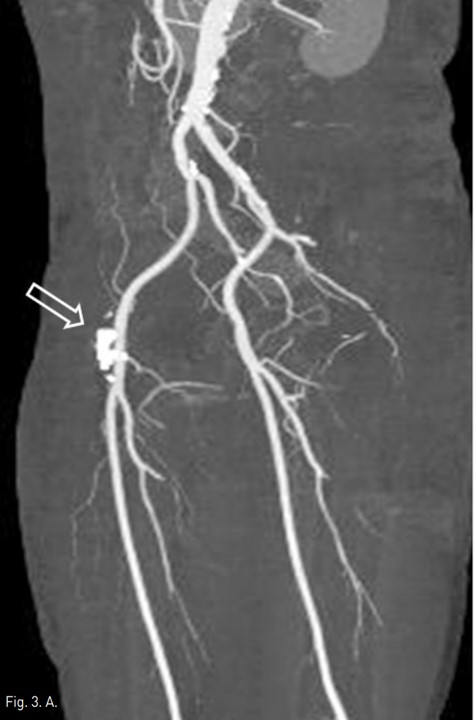

Fig. 3. A

Fig. 3A, B. 3D volume rendering with left anterior oblique projection image (A) obtained 12 days after procedure shows glue complex (arrow) in the pseudoaneurysm with no residual filling of contrast media. Also, color doppler US (B) obtained the same day shows complete obliteration of pseudoaneurysm(asterisk) with the patent common femoral and medial circumflex femoral arteries.